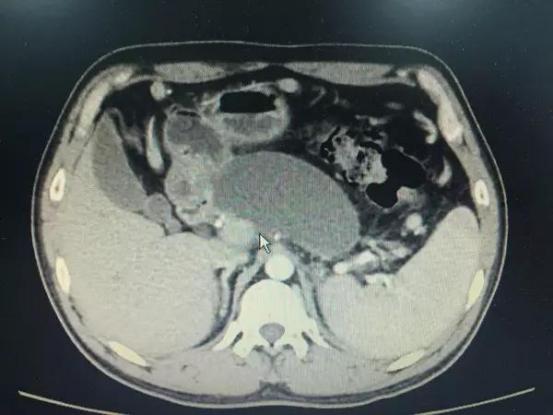

术前CT检查见巨大胰腺假性囊肿形成

此次患者郑某、耿某均于半年前发生胰腺炎,病情稳定后逐渐出现腹胀、进食后呕吐等梗阻症状,入院后经CT检查发现巨大胰腺假性囊肿形成。我院东院消化内科以张春清主任、张俊勇副主任医师为首的超声内镜介入团队,带领冯华主治医师、王广川主治医师,结合疾病特点和既往经验,反复研究琢磨,借鉴先心病室间隔缺损“封堵器”的原理,创新采用特制双蘑菇头覆膜支架代替传统胆道支架,通过膨大的双蘑菇头将胃壁和囊壁牢牢卡在一起,从而避免支架滑脱的可能,另外宽大的蘑菇头使术者可以轻松的操作鼻胃镜经支架中间孔道进入囊腔,进而对囊内坏死物质进行冲洗和清理,促进患者恢复。两位患者在植入双蘑菇头支架后,腹胀症状迅速缓解,即可正常饮食,经4周引流,复查CT囊肿基本消失,支架无任何移位,遂在内镜下将支架取出,胃壁创口愈合良好。